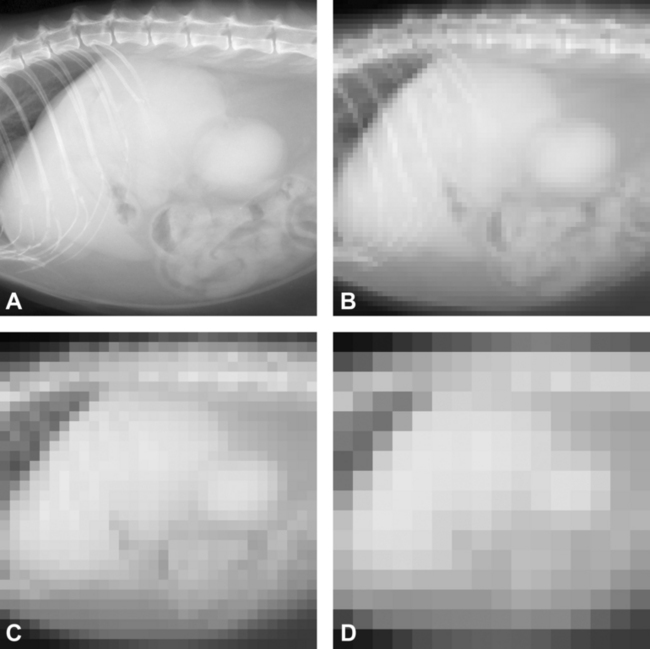

Figure 22-8 The effects of matrix and pixel size on image resolution are illustrated in this series of otherwise identical lateral cat abdominal radiographic images. A, A high-quality digital image with a high matrix size (e.g., 2048 pixels on the vertical axis × 2048 pixels across the horizontal axis). B, The matrix size is reduced to 64 × 64 pixels. Note that individual pixels can be seen as small squares, and the image has a pixilated appearance. C, The pixilation becomes noticeably worse when the matrix size is reduced to 32 × 32. D, The matrix size is only 16 × 16 pixels, and the image of the cat abdomen is no longer recognizable. Note that each pixel only represents a single shade of gray, dependent on bit number.